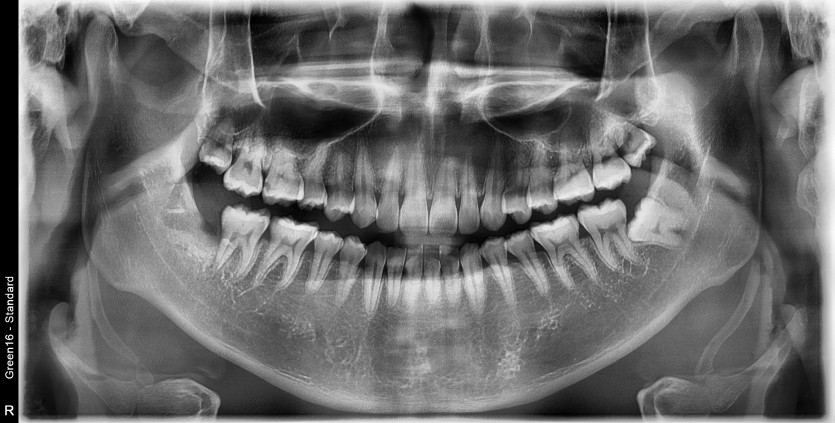

#48 사랑니 발치

구강 외과 전문의가 당일 발치했습니다.